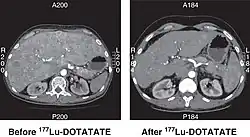

![]() CT scan of non-functioning pancreatic NET before and 6 months after successful treatment with four cycles of 177Lu-DOTATATE. | |